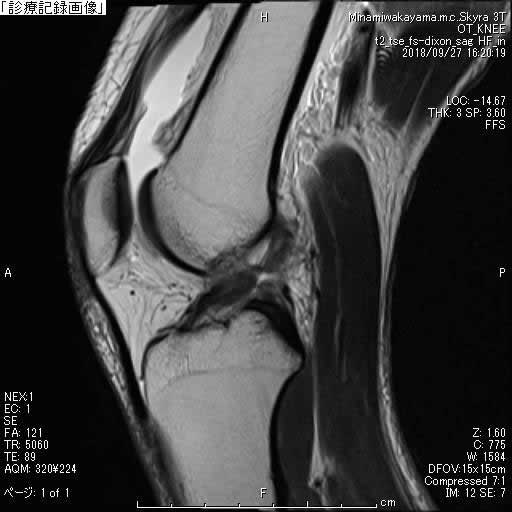

MRI

損傷部位や合併症を評価します。

どのような損傷が起こっているかを把握することができます。

また、半月板内部の評価にも有効であり、変性の有無を推測することにも役立ちます。